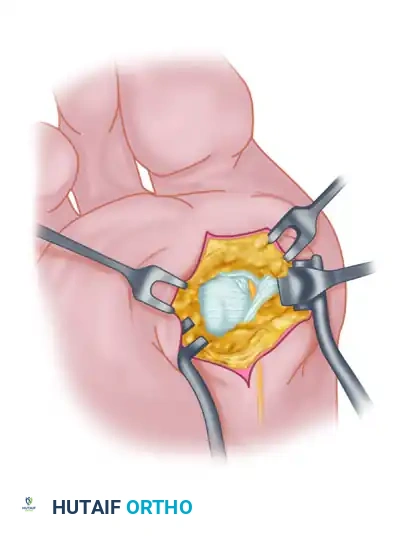

Fibular (Lateral) Sesamoidectomy: Dorsal Approach

In the modern Modified McBride procedure, the fibular sesamoid is rarely excised. However, if a severe, rigid valgus deformity persists after a complete adductor release and lateral capsulotomy, and the sesamoid cannot be mobilized, a fibular sesamoidectomy may be indicated.

- Adequately separate the first and second metatarsal heads using a lamina spreader or Inge retractor.

- Plantarflex the MTP joint 10 to 20 degrees to reduce tension on the sesamoid apparatus.

- Grasp the fibular sesamoid firmly with a small Kocher clamp or sturdy tissue forceps, pulling it laterally into the intermetatarsal space.

- Carefully release the intersesamoid ligament. Once incised, the fibular sesamoid can be delivered into the intermetatarsal space for straightforward removal.

- Surgical Warning: Extreme care must be taken when incising the intersesamoid ligament to avoid severing the flexor hallucis longus (FHL) tendon, which lies immediately plantar to it. If the FHL is inadvertently severed at this level, it generally should not be repaired, as repair often results in a rigid, fixed flexion contracture of the interphalangeal joint, whereas loss of the tendon causes minimal functional impairment.

- Alternative to Excision: Release part or all of the FHB lateral head at its insertion into the fibular sesamoid. Remember, performing both a metatarsal osteotomy and a fibular sesamoidectomy drastically increases the risk of iatrogenic hallux varus.